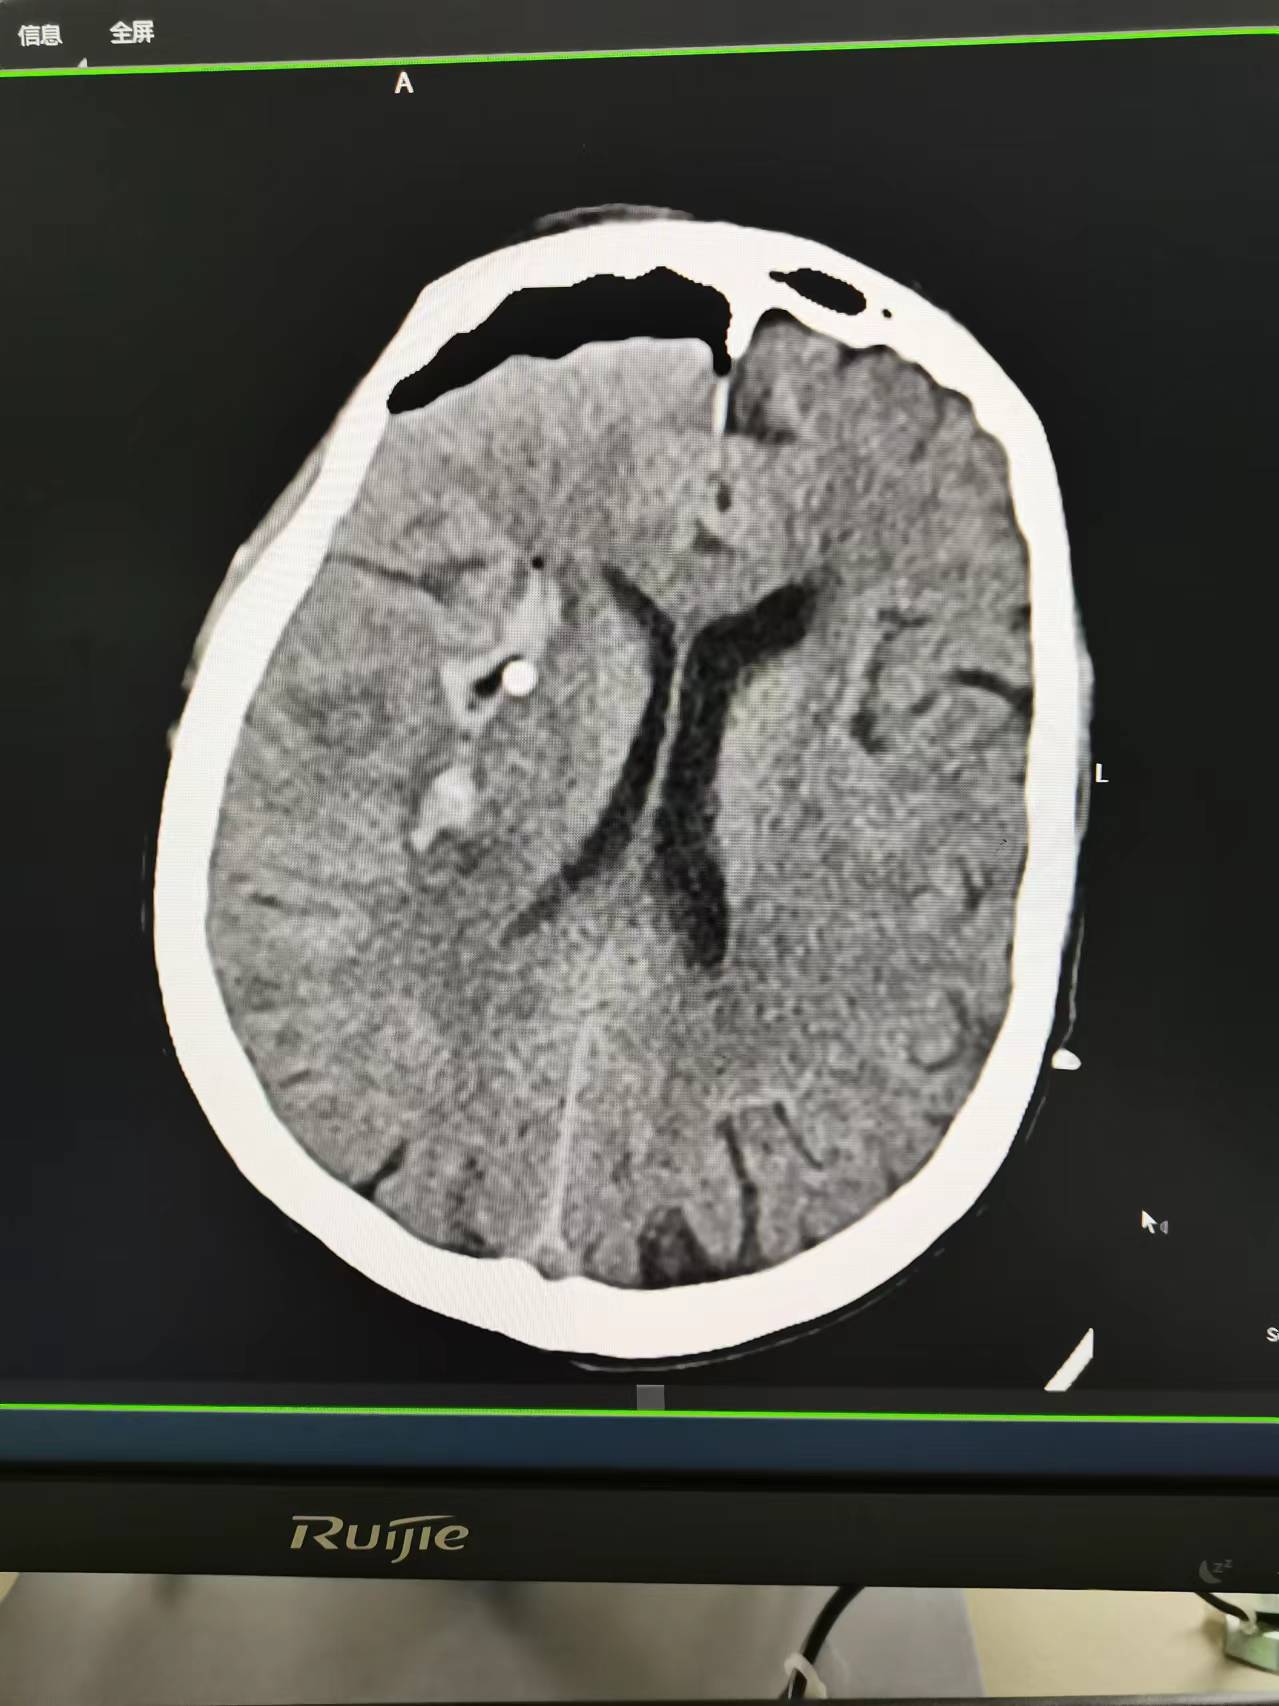

手术切口

手术骨瓣还纳